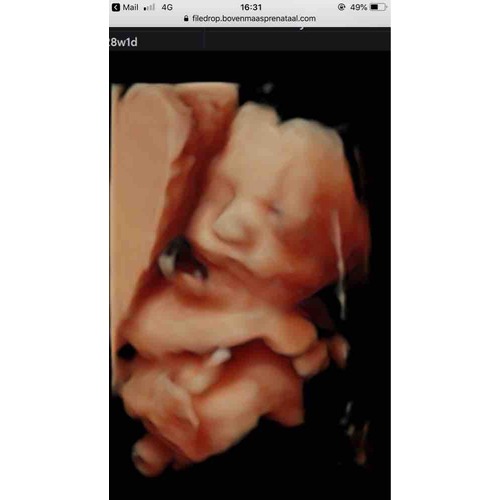

Bij mijn vorige zwangerschap had ik bij 27 weken een 2D echo, en hebben ze zelfs even op 3D gezet dus alsnog een mooie 3D foto erbij gekregen. Voor deze zwangerschap ga ik weer rond die weken plannen en er werd mij gezegd dat een 3D echo lastig word vanwege placenta dus sowieso weer 2D en dan vragen we gewoon weer hetzelfde ☺️

Ik wil het zelf wel laten doen maar ik zou nog even wachten tot je over de 29 a 30 weken bent. Denk dat je dan het beste beeld van je kleintje krijgt, het is dan toch wat verder gevorderd qua ontwikkeling denk ik

Wij gaan ook! Ze zeiden dat het het beste beeld is tussen 26/28 weken. Later niet. Wij gaan met 27 weken💕

Bij ons doen ze het vanaf 26 weken, niet eerder. Wij gaan als ik bijna 28 weken ben. Moet eerlijk zeggen dat ik vooral voor een pretecho wil omdat ik de tijd tussen de echo’s anders zo lang vind hahaha